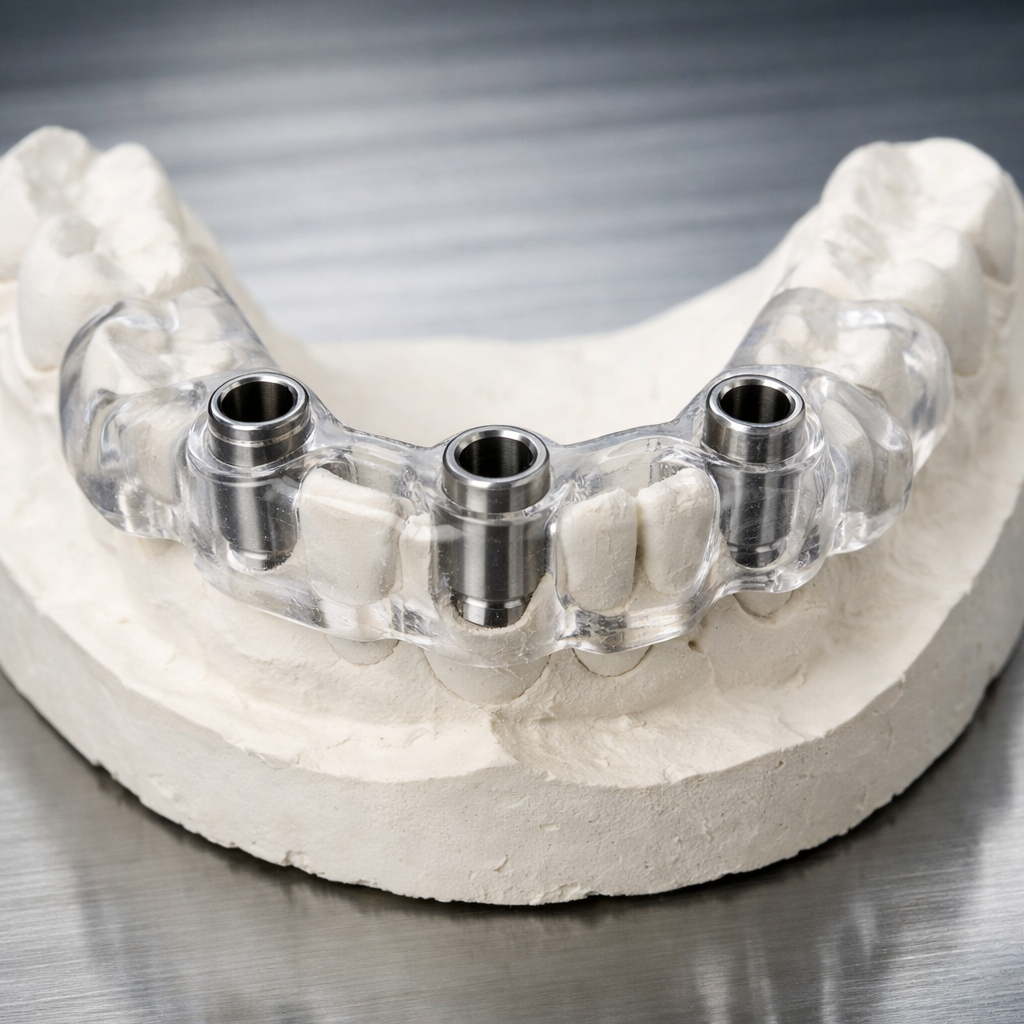

즉시 임플란트의 성패는 심는 순간 결정됩니다. 보통 35Ncm 이상의 토크(Torque)로 고정되어야 하며, 이를 위해 3D 디지털 가이드를 활용해 가장 단단한 뼈 위치에 정교하게 식립하는 것이 핵심입니다. 고정력이 확보되면 당일 임시 치아 제작까지 가능해집니다.